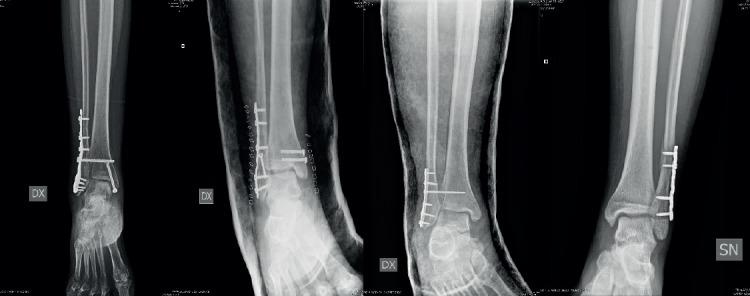

Tubular vs Profile Plate in Peroneal or Bimalleolar Fractures: is There a Real Difference in Skin Complication? A Retrospective Study in Three Level I Trauma Center.

This study is a retrospective single-centre study in which was performed plating of fibula in closed ankle fractures. 93 patients were included in our study and assigned in two groups, based on using of different implant : in group A 48 patients were treated with one-third tubular and in group B 45 patients were treated with LCP distal fibula plate. There were no significant differences in the baseline characterisctics. Patients received the same surgical procedure and the same post-operative care, then they were radiologically evalueted at 1-3-12 months and clinical examination was made at 12 months using AOFAS clinical rating system. Categorical data, grouped into distinct categories, were evalueted using Chi-square test. We considered a p value < 0.05 as statistically significant.

The wound complications rate of the overall study group was 7.6%. There were no statistical differences in the rate of wound complications between the two groups. There were no differences between both group in percentage of hardware removal at follow-up (overall 5.4%); plate removal was performed earlier in the locking plate because of wound complications.

本研究为回顾性单中心研究,纳入闭合性踝关节骨折行腓骨钢板固定的患者。93例患者根据所使用的不同植入物分为两组:A组48例患者接受三分之一管型钢板治疗,B组45例患者接受LCP腓骨远端钢板治疗。两组患者的基线特征无显著差异。患者接受相同的手术操作和术后护理,术后分别于1个月、3个月和12个月进行影像学评估,并在12个月时使用美国足踝外科协会(AOFAS)临床评分系统进行临床检查。分类数据采用卡方检验进行评估。我们将p值<0.05视为具有统计学意义。

整个研究组的伤口并发症发生率为7.6%。两组之间的伤口并发症发生率无统计学差异。两组随访时取出内固定物的比例无差异(总体为5.4%);由于伤口并发症,锁定钢板组的钢板取出时间更早。